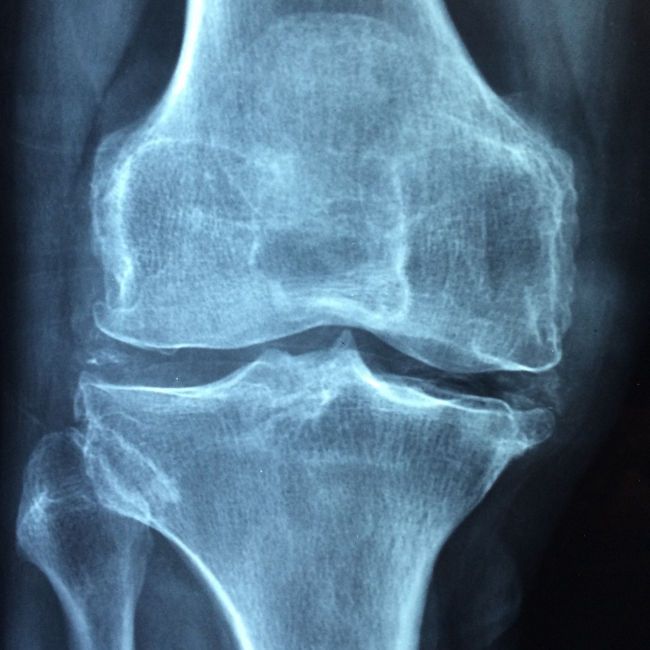

Коленный сустав – один из самых сложных по строению. Врожденные или приобретенные деформации его составляющих привносят дополнительные трудности в процесс замены сустава, с которыми бывает непросто справиться даже опытным хирургам. В результате пациенты могут вскоре после операции столкнуться с нестабильностью сустава, нарушением его функций и быстро стать кандидатами на повторное вмешательство. Избежать подобных проблем можно с помощью хирургического робота, обеспечивающего исключительную точность замены сустава.

- создание модели сустава на основе 3-мерной модели по результатам компьютерной томографии. Компьютерная программа позволяет определить оптимальную резекцию и расположение фрезевых отверстий в костях, что обеспечивает идеальное позиционирование имплантата для конкретного пациента;

- операция по замене коленного сустава. Хирург осуществляет доступ к суставу и совмещает его ориентиры с ключевыми точками, заложенными в компьютерной программе робота. Затем роботизированная система CUVIS-joint с субмиллиметровой точностью реализует план по резекции пораженных тканей и создает каналы для крепления эндопротеза сустава. Далее устанавливается имплантат и проводится тестирование его функционирования. Операция завершается ушиванием мягких тканей.